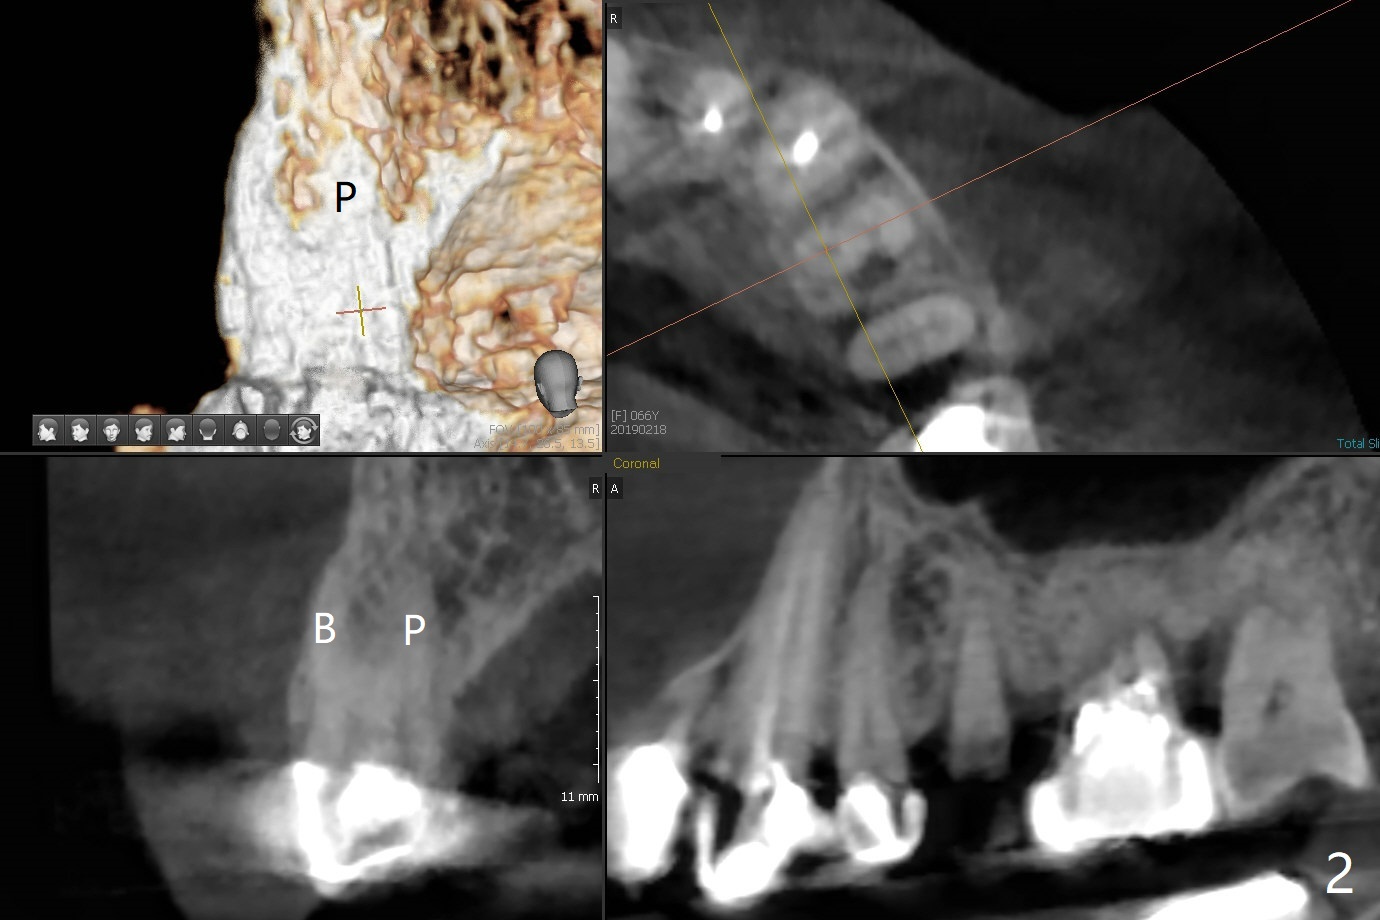

68岁女右上4个植牙后(图一),左上4(12号牙)根尖周围炎,根管闭锁(图二),牙周袋9毫米。切割3,4连冠,拔除4,为了减少腭侧骨板吸收,植体也不要植入太腭侧(图三,四)。其实顺腭侧根钻洞偏近中,很难纠正,最后位点保存